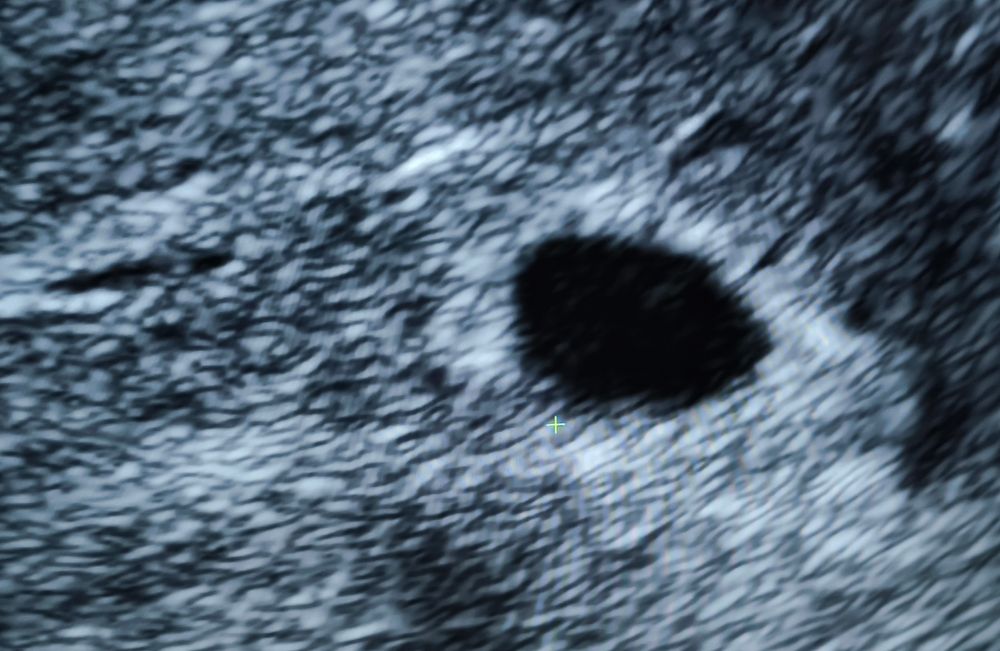

В итоге, садимся мы на УЗИ аппарат. Находит "врач" плодное яйцо, а оно пустое... У меня понятное дело паника, говорю может у вас с аппаратом что то не то? (Качество картинки было в разы хуже). На что врач зачитала мне лекцию "большинство беременностей заканчивается выкидышами, и ты не исключение, УЗИ плохое, аппарат у меня лучший, так что в понедельник контрольный прием и потом будем решать что делать (чистка).

Я очень надеялась что моя чуйка и хгч (которое растет) меня не подводит поехала сразу к первому врачу. Меня проверили и в сложном яйце все на месте и все хорошо. Вывод из истории я больше не ищу врача! А остаюсь с первым. А таким "специалистам" с плохой техникой руки бы пообрывать. Или научиться сообщать новости.... Прикрепляю фото УЗИ с разницей в 20 минут (на разных аппаратах) . Боюсь представить сколько таких беременностей было объявлено развивающимся.